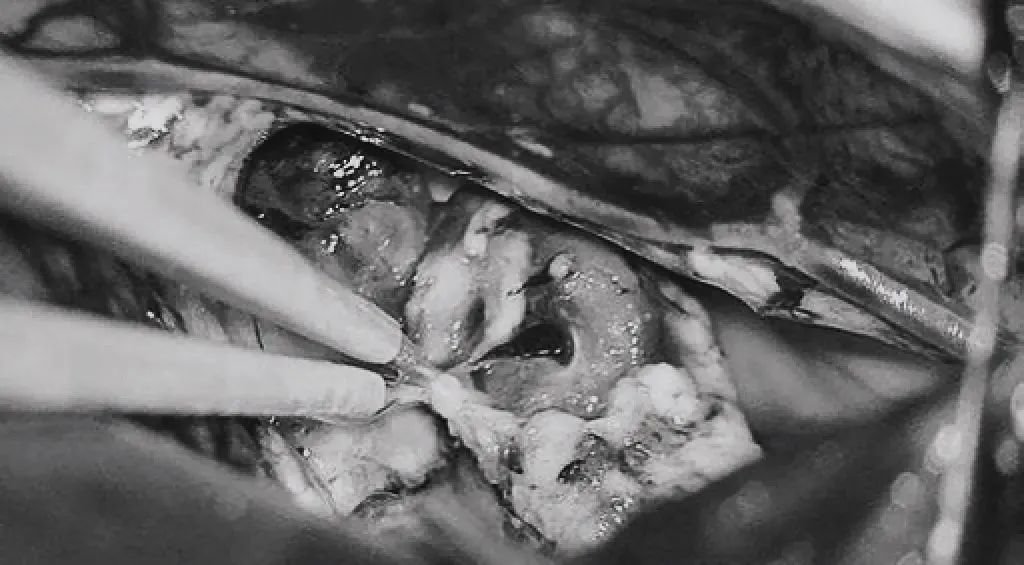

▼双额开颅,打开纵裂(鼻朝右,中线水平位,重力牵拉右侧半球),显露胼胝体、CmaA和PcaA。切开胼胝体2.5cm,显露透明隔内的AVM,大致显露ACA。

▼将AVM后缘向前牵离穹窿。

▼在透明隔底部保留FoM、穹窿和右侧SepV。

▼引流静脉变黑。

▼引流静脉进入ICV处电凝。完全切除AVM。